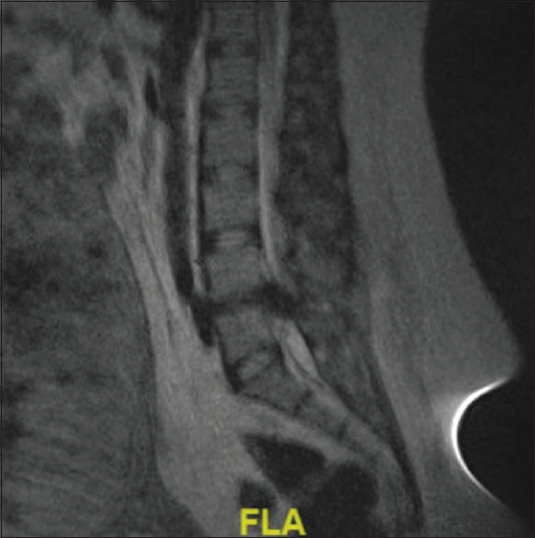

Pregnancy-induced changes to spinal anatomy and physiology can increase the complexity of neurosurgical intervention in this population. There are numerous reports focused on the neurosurgical management of intracranial pathology for pregnant patients. However, less is known about the neurosurgical management of acute spinal pathology. This study aims to discuss the management of emergent spinal pathology during late-term pregnancy. This is a case series of acute spinal pathologies in pregnancy. Epidural spinal needle fracture, epidural abscess, disc herniation causing an acute neurological deficit, and potential spine trauma. An extensive literature search relevant to the operative cases was performed to highlight the relevant themes to management. (1) The epidural spinal needle fracture was managed by surgical exploration under local anesthesia. (2) The epidural abscess was managed with laminectomy and surgical evacuation of the infective mass under general anesthesia. (3) The acute disc herniation was managed with laminectomy and discectomy under general anesthesia. All three examples were managed with emergent surgeries with improvement of symptoms. (4) The potential spine trauma was managed nonoperatively. Relevant similar cases from the literature review were summarized and strategies for management were outlined. Several factors such as anesthesia type, positioning, and operation sequencing must be considered when managing acute spinal pathology in late-term pregnant patients, necessitating multi-disciplinary input. However, effective management can result in successful surgical intervention and improvement of symptoms.